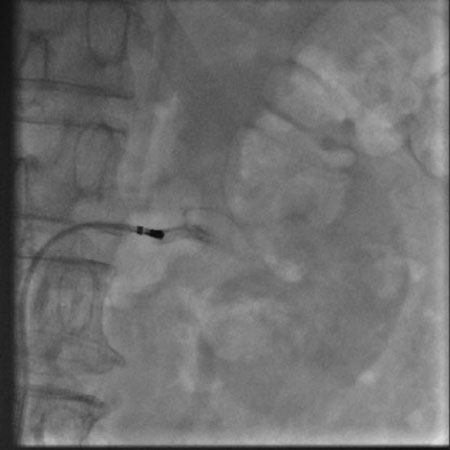

肾动脉造影(左)

2月6日,我院心内科在上海普陀区中心医院心内科刘宗军主任指导下开展了我省首例肾动脉交感神经射频消融术。目前患者病情稳定,一周后复查动态血压,平均收缩压已从术前157mmHg降至137mmHg,患者已出院在继续随访中。

肾动脉交感神经射频消融术用于难治性高血压的治疗,于2008年在美国首先应用于临床,属介入手术,只需穿刺肾动脉进行手术,治疗完成后1—3月内患者血压即可明显下降,最大降幅可达30—40mmHg。术后患者服用少量降压药物即可将血压控制在良好水平,部分患者可以永久摆脱降压药物。从而避免了终生服用降压药带来的经济负担、生活不便和副作用影响。